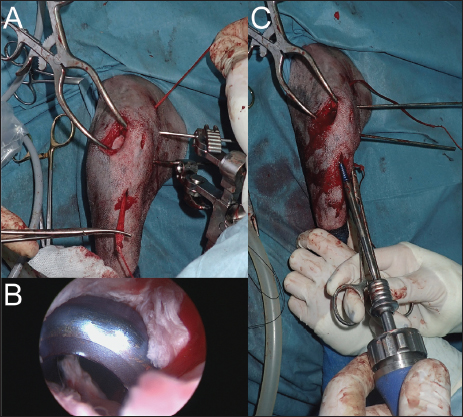

The dog was anesthetized with tiletamine (0.5 mg/kg)/zolazepam (0.5 mg/kg) + medetomidine (0.01 mg/kg) + morphine hydrochloride (0.5 mg/kg) by induction. An isoflurane relay (between 0.8 and 1%) in half-closed circuit was carried out at a flow rate of 1 l/minute. A constant rate infusion (2 ml/kg/hour) of a mixture of 250 ml of physiological serum + 30 mg of morphine + 202.75 mg of lidocaine + 75 mg of ketamine was administered. A single injection of cephalexin at 30 mg/kg was given at the start of the surgical preparation. The dog was placed in dorsal recumbency and prepared for aseptic surgery on the right hindlimb using chlorhexidine. A joint distractor supported by two 2.5-mm pins was placed on the stifle. The arthroscopic port was placed on the lateral side through a 5-mm lateral parapatellar incision performed with an 11-mm blade. Arthroscopic evaluation of the joint revealed inflammation of the medial meniscus without structural damage (Fig. 2A) and confirmed the complete rupture of the CdCL in its distal part at the tibial insertion (Fig. 2B). The lateral meniscus and the cranial cruciate ligament were intact. The lateral parapatellar incision was made 3 cm wider to allow the complete resection of the damaged CdCL with an 11-mm blade under arthroscopic control. The bone tunnels for femoral and tibial fixation of the synthetic ligament were drilled under arthroscopic control. A 2-mm guide wire was inserted at the femoral footprint of the origin of the CdCL in a caudo-medial direction to exit on the medial side of the femoral condyle under arthroscopic guidance. The femoral tunnel was drilled over the guide wire using a 3.6-mm cannulated drill bit (Fig. 3A). The tibial tunnel was created with the help of a tibial drilling guide. A stab incision was made at the caudal aspect of the joint to insert the tip of the tibial drilling guide, which was positioned at the footprint of the proximal tibial insertion of the CdCL under arthroscopic control, and oriented in a distal and cranio-lateral direction. A stab incision was made on the proximal aspect of the craniolateral aspect of the tibia to position the sleeve of the drilling guide. The appropriate position of the tip of the tibial drilling guide was assessed arthroscopically before drilling. The same technique as that used for the femoral tunnel was used to drill the tibial tunnel (Fig. 3B). The UHMWPE implant (Novalig 4000, Novetech Surgery, Monaco) was passed through the tibial and femoral tunnels using a passing tube and a wire loop (Fig. 4A). A 4.5 × 20-mm interference screw was placed from inside-out (Fig. 4B) (Rafael et al., 2020). The UHMWPE implant was then passed through a 3-mm-wide sliding tunnel, drilled perpendicularly through the tibial crest using a medial approach and located near the distal exit of the tibial tunnel. This setup increased the precision of the tensioning of the prosthesis using the created counter-support and facilitated the placement of the interference screw. Once satisfactory tension was obtained, the implant was locked with a second 4.5 × 20-mm interference screw placed from outside-in (Fig. 4C) (Rafael et al., 2020). Once the implant was securely locked, no residual drawer sign was observed and a normal range of motion was reported.

Fig. 3. (A) Femoral tunnel drilling. (B) Insertion of the 2-mm guide wire from lateral tibial metaphysis to CdCL tibia insertion under arthroscopic guidance.

Fig. 4. (A) Placement of UHMWPE implant. (B) Arthroscopic view of femoral interference screw insertion. (C) Prosthesis tensioning and insertion of tibial interference screw.